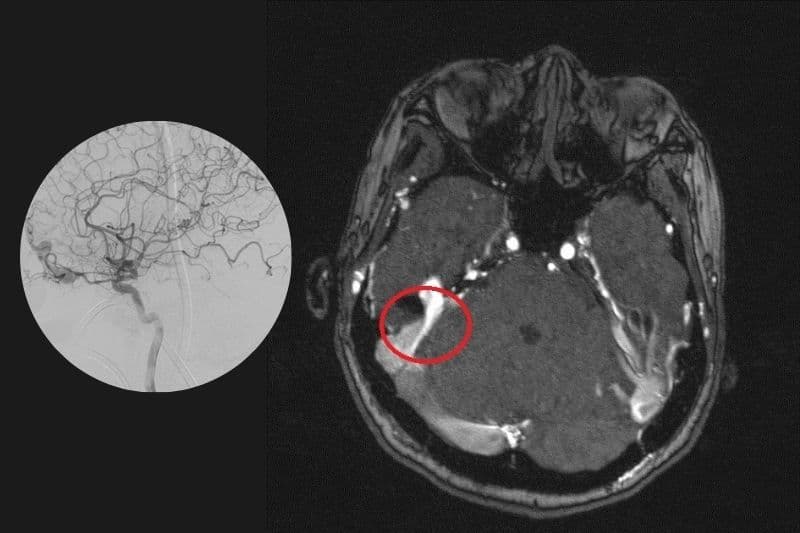

2.1. Dị dạng động – tĩnh mạch (AVM)

Đây là dạng phổ biến và nguy hiểm nhất, khi động mạch nối trực tiếp với tĩnh mạch mà không qua mao mạch trung gian. Dòng máu áp lực cao từ động mạch đổ thẳng vào tĩnh mạch khiến thành mạch dễ bị giãn, yếu và có nguy cơ vỡ. Tình trạng này làm tăng nguy cơ xuất huyết não, đặc biệt ở người trẻ tuổi không có yếu tố chấn thương.

- Chụp cộng hưởng từ (MRI): Phương pháp quan trọng trong chẩn đoán dị dạng mạch máu não nhờ khả năng hiển thị chi tiết cấu trúc mô mềm. Kỹ thuật này giúp xác định vị trí, kích thước và ảnh hưởng của dị dạng đến mô não xung quanh.

- Chụp cắt lớp vi tính (CT): Cung cấp hình ảnh nhanh và hữu ích trong phát hiện xuất huyết não cấp tính do vỡ dị dạng. Khi kết hợp với thuốc cản quang, phương pháp này giúp quan sát rõ hệ thống mạch máu bất thường.

- Chụp mạch não: Kỹ thuật chuyên sâu giúp quan sát trực tiếp dòng chảy trong hệ mạch máu não. Phương pháp này thường được sử dụng khi cần đánh giá chi tiết qua chụp dị dạng mạch máu não trước khi can thiệp điều trị.